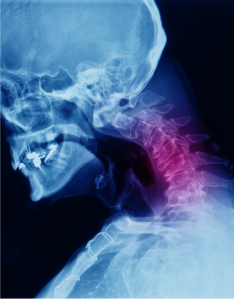

Neck Pain

The first 7 vertebral bones on the spinal column form the cervical spine and are located in the neck region. The neck bears the weight of the head…

Cervical Radiculopathy & Myelopathy

The spine, also called the back bone, is designed to give us stability, smooth movement, as well as providing a corridor of protection…